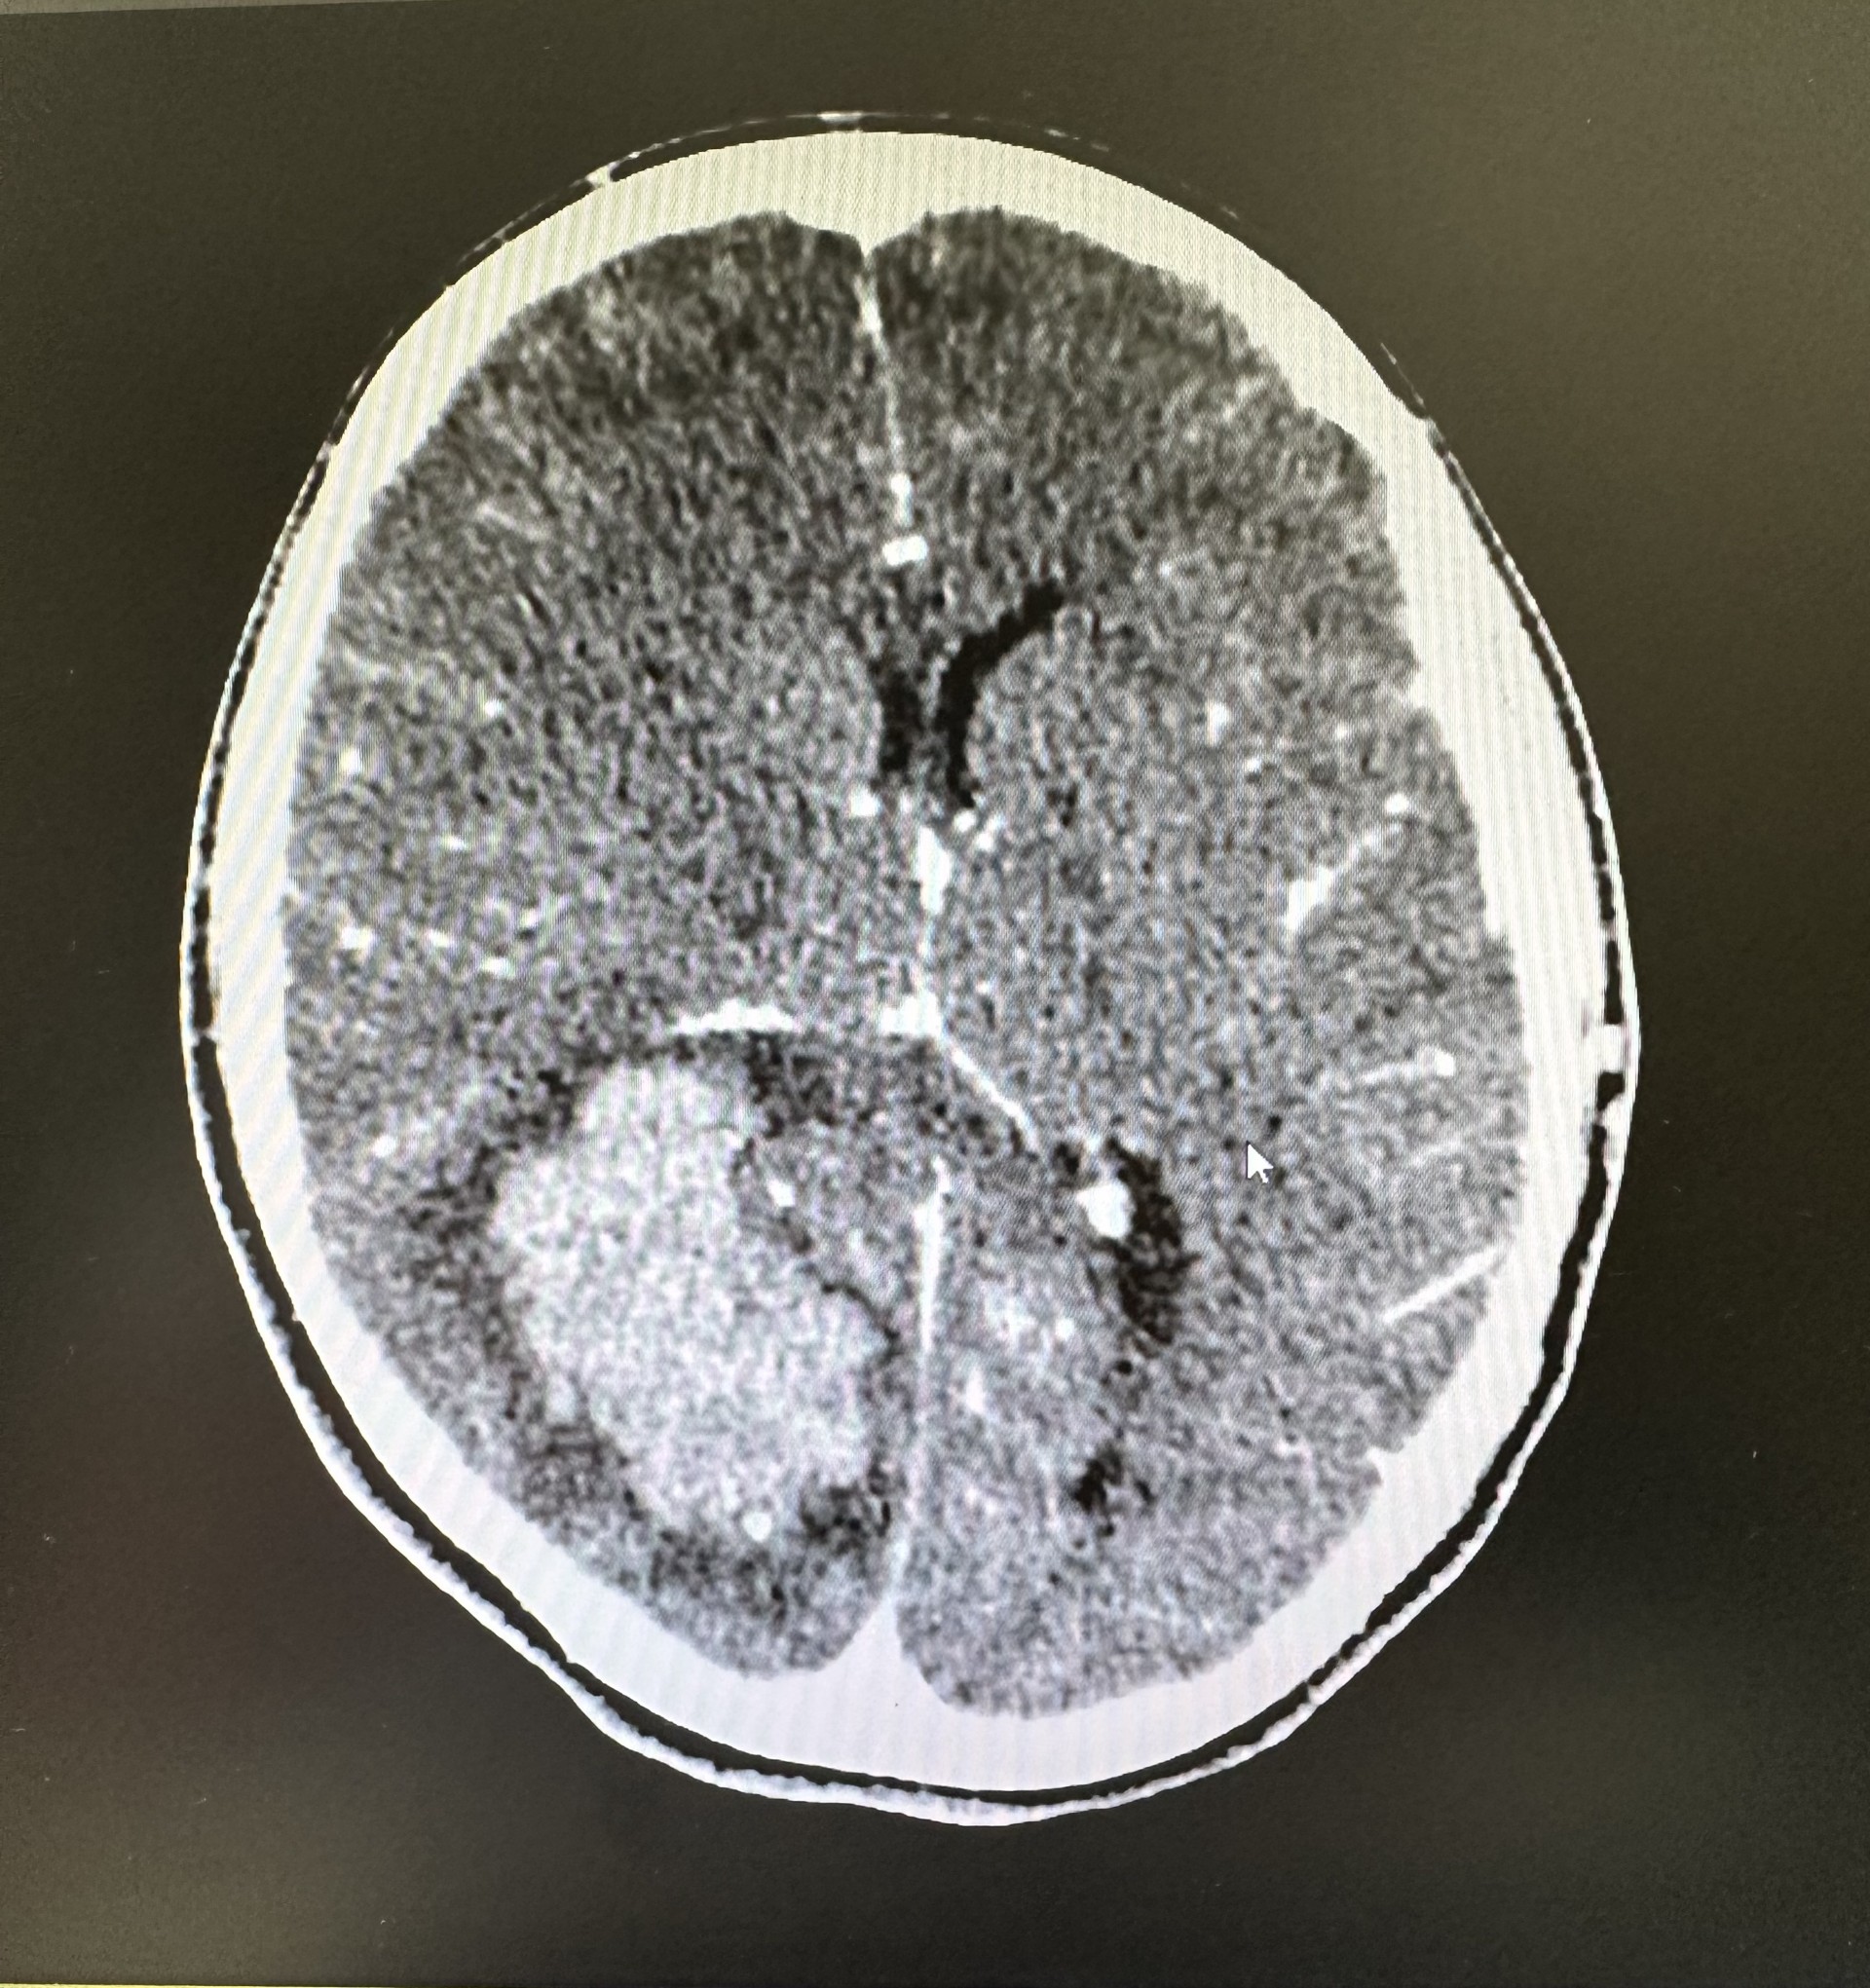

• Juicio clínico: La paciente es derivada al Servicio de urgencias hospitalarias. Se realiza TAC craneal simple y con contraste diagnosticando de hematoma intraparenquimatoso parietooccipital derecho. Se realizó posteriormente arteriografía, observando que dicho sangrado era secundario a una malformación arteriovenosa occipital parasagital hemisférica derecha.

• Tratamiento y planes de actuación: intervenida de forma emergente de con craneotomía evacuadora y clipaje de 2 aneurismas.